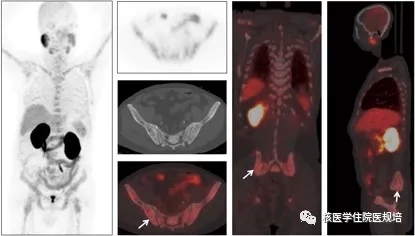

患者男性,75岁,因“前列腺癌术后9年,腰痛1月”就诊。患者9年前因前列腺癌行根治性前列腺癌切除术(T1N0M0, Gleason评分4+3),术后行内分泌治疗9年,近期因腰痛入院。实验室检查:前列腺特异性抗原(PSA):0.45 ng/mL(参考值:0-4 ng/mL)。为协助除外骨转移行99mTc-MDP全身骨显像检查(图1)。

图1:99mTc-MDP全身骨显像

检查所见:

静脉注射99mTc-MDP 4小时后行全身前、后位平面显像。影像所见:全身骨骼显像清晰,颅骨、脊柱、胸骨、双侧肩胛骨、双侧肋骨、骨盆诸骨、双侧股骨近端及右侧肱骨近端可见多发异常放射性浓聚灶,双肾及膀胱未见显影,软组织本底示踪剂摄取减低,呈“超级显像”表现。

检查意见:

全身骨多发血运代谢增强灶,结合病史,考虑为前列腺癌多发骨转移。